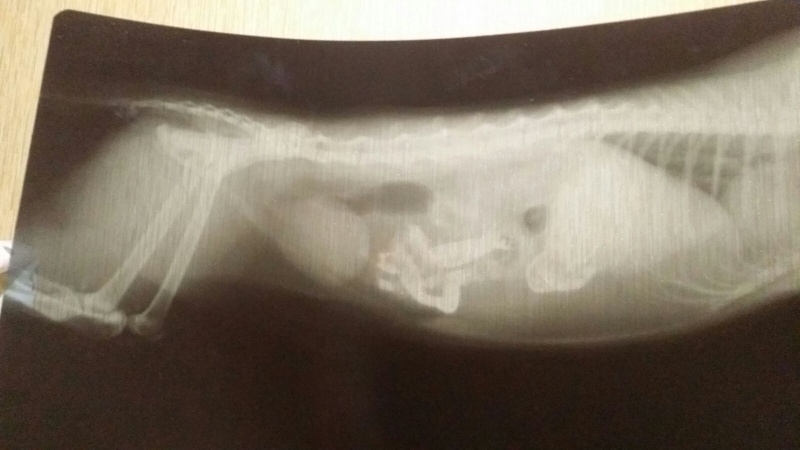

вечером Джуну опять вырвало с барием, Ксюша свозила ее в АС ВЕТ - там поставили серению по весу, чтобы не было рвоты. задала барий повторно в час ночи, утром вчера повезла на ренген. заключение - непроходимость. Как такового предмета не обнаружено, но взвесь бария стоит.

сегодня сделали повторный рентген - барий уже скомковался, но стоит где был, немного продвинулся из-за съеденной пищи. всё.... забрали на операцию.....